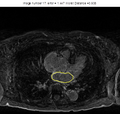

Results

The example of extracted ridges is shown in the Figure 1. The connected boundary is shown in the Figure 2. For the tested volumes, when comparing the obtained boundary with expert's manual segmentation, the average distance error is about 2 pixels. The results of GVF active contour approach are shown in the Figures 3-5. The bright gray contour is the expert's segmentation, and yellow contour is the result of our algorithm. The average distance error there is less than 2 pixels.